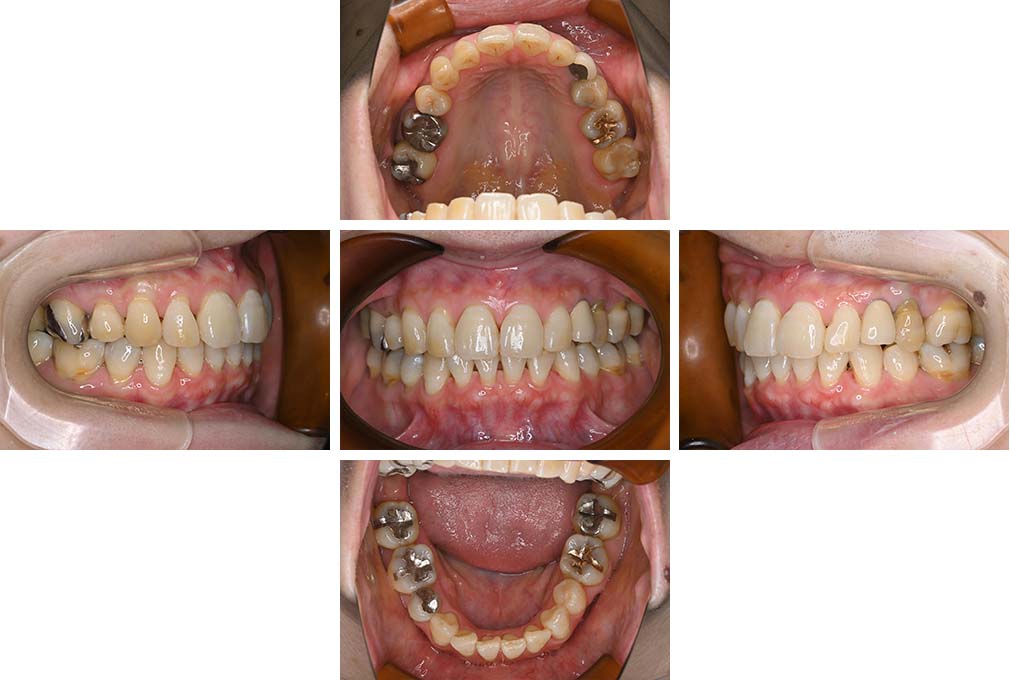

CASE:01

叢生を伴う骨格性上顎前突

初診時年齢 15歳10カ月

性別 男性

治療費の目安 約75万円程度(治療開始時)

上顎前歯の前突と叢生を主訴として来院された。大臼歯関係は左右側ともにⅡ級で上顎の方が前方に位置していた。叢生を伴う骨格性上顎前突と診断し、上下顎小臼歯抜歯を行っていただきマルチブラケット装置に顎外固定装置を併用して動的治療を行った。顎外固定装置や矯正用ゴムの使用など協力状態も良好で、動的治療期間2年0カ月、調整来院20回でマルチブラケット装置を撤去し保定へ移行した。動的治療終了後10年0カ月を経過したが保定移行時とほぼ同様の咬合状態で良好な状態を保っていた。

治療前

15歳10か月

治療後

動的治療期間2年0カ月

18歳5か月

10年経過

動的治療終了後10年0カ月

28歳5か月